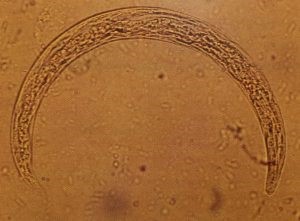

L’angiostrongylose est une maladie parasitaire transmise par le nématode

(le vers rond Angiostrongylus vasorum) qui réapparaît avec le retour des escargots et limaces dans les jardins.

Coproscopie Baermann (Prélèvements de selles 3 jours consécutifs) pour recherche des larves